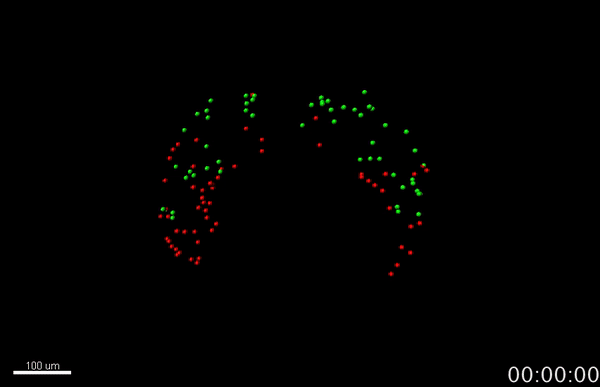

During vertebrate heart development, two progenitor cell populations; first and second heart fields (FHF and SHF), sequentially contribute to heart tube formation and subsequently form the mature heart5,13. In view of that, cells in the developing mouse embryo were fluorescently labelled with genetic tracing tools, for 4D cell tracking and live-imaging cardiac differentiation over time with cellular resolution, for the first time. A culture system14 was reproduced, to allow embryonic growth externally, while immobilized for live imaging, to ensure the developing whole mouse embryo was stable throughout the process of live-imaging early cardiogenesis (Fig 4A)5. The system, coupled to live-confocal and -multiphoton microscopy, enabled high-resolution images (Fig 4B) and 4-D movies via time-lapse acquisition (Fig 5-7)5.

Live-imaging and 4-D cell tracking experiments sequentially captured dynamics of cell differentiation and cell movement during early heart tube formation to uncover cell population-based co-ordination of heart tube morphogenesis5. Three distinct stages of heart tube formation were observed with time to reveal 1) an early phase where cellular precursors differentiated to form a cardiac crescent, 2) followed by a 2nd phase to form a dorsally open heart tube and 3) a final phase of its dorsal closure5. Representative figures outline key features of the study (Fig 5-7)5.

The study further enabled quantification of cardiac cell differentiation during heart tube formation, using the 4D microscopy time-lapse movies and Imaris software, where each object (cell of interest) was identified according to pixel intensity (Fig 7). Study limitations included inability to image all cells located inside live tissue at the final stages recorded with multiphoton-imaging, due to limited depth of penetration, overcome by fixing embryos post-live-imaging for confocal microscopy analysis5. Further studies will also be required to verify key observations detailed.